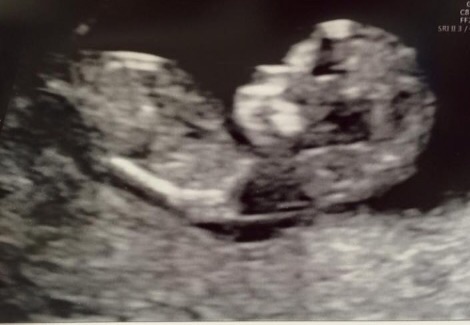

Boy or girl please?!

Hi, any help greatly appreciated. Thanks!

No clues on there sorry :)